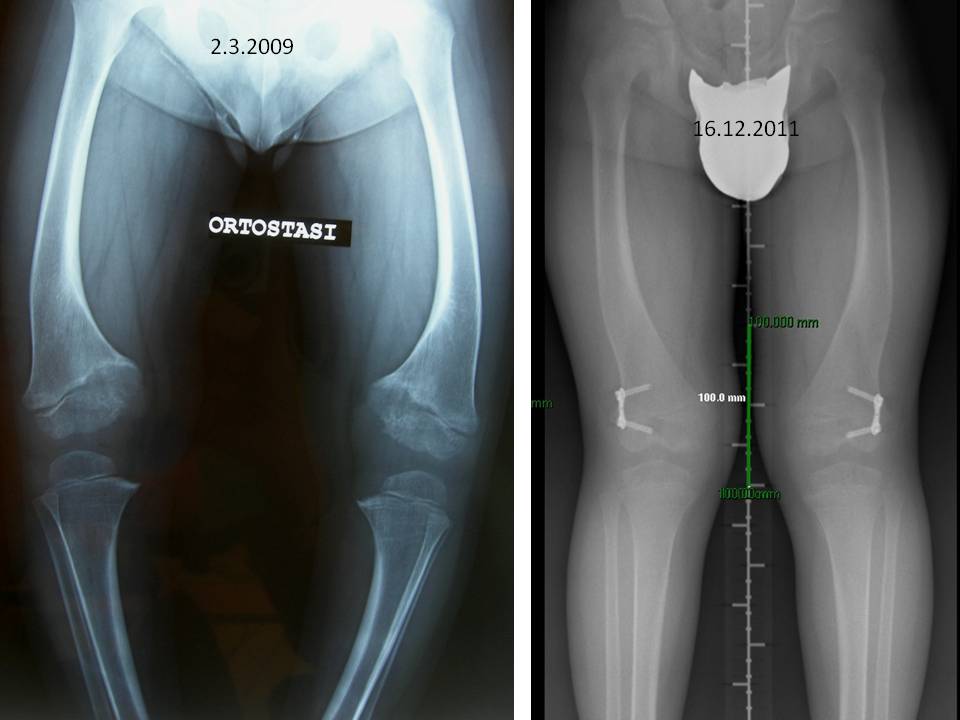

Fig. 10: rachitismo vit. D resistente

Fig. 10: Rachitismo vit. D resistente. Aspetto radiografico prima e dopo circa 30 mesi dall’intervento di epifisiodesi asimmetrica. E’ evidente il cambiamento dell’asse delle ginocchia ottenuto gradualmente con l’applicazione delle placche a “8” che determinano una crescita guidata degli arti inferiori. L’intervento non richiede alcuna immobilizzazione in gesso e la ripresa del carico è possibile rapidamente secondo tolleranza.